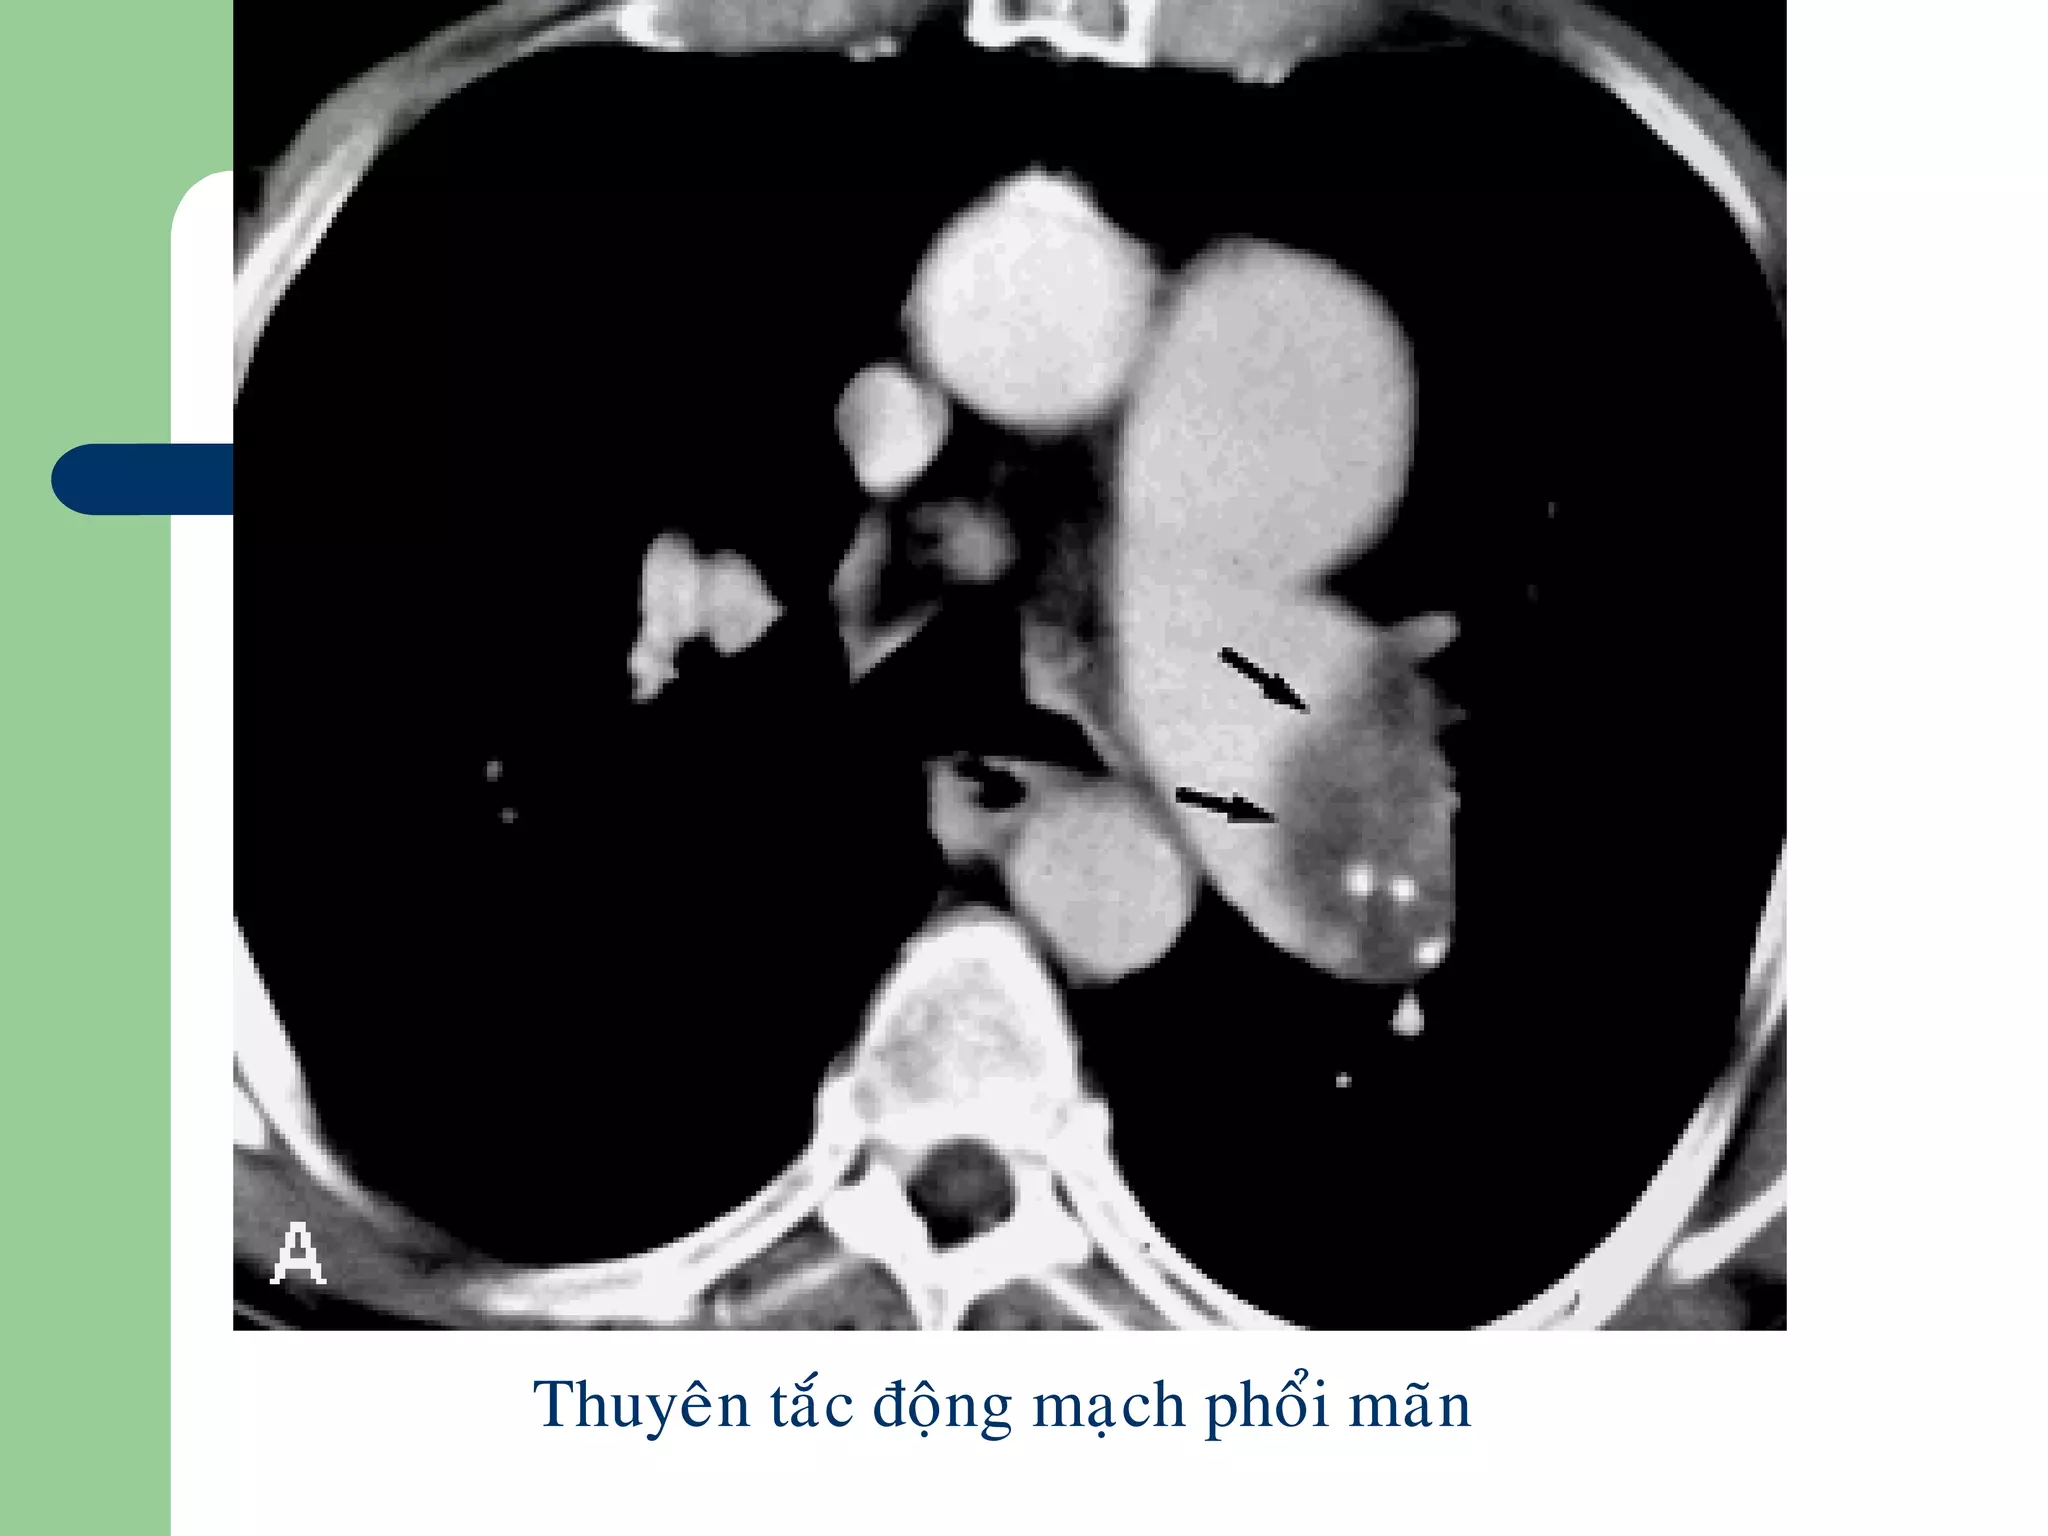

Thuyên tắc phổi

 Khuyết trong lòng mạch do cục máu

đông

 Vùng tăng đậm độ hình chêm, nền dựa

vào màng phổi (nhồi máu phổi)

 Tăng quang ngoại vi

 Rối lọan thông khí

Thuyeân taéc ñoäng maïch phoåi maõn